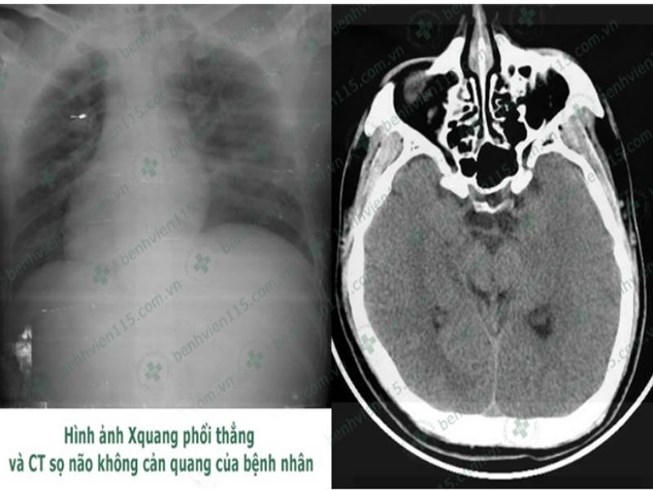

Trước đó, anh N. được đưa vào BV trong tình trạng hôn mê sâu, thở nhanh, phổi đầy ran nổ hai bên (ran nổ là loại tiếng phổi không liên tục, ngắn hơn 9 mili giây, thô ráp, nghe rõ nhất cuối kỳ hít vào, chứng tỏ có sự hiện diện của dịch hay chất xuất tiết trong phế nang - PV).

Các BS chẩn đoán bệnh nhân N. hôn mê sâu do hạ đường huyết kéo dài và bị viêm phổi nặng. Bệnh nhân được hỗ trợ hô hấp bằng máy thở và truyền đường với nồng độ ưu trương để nâng mức đường huyết về bình thường. Tuy nhiên tri giác bệnh nhân vẫn không cải thiện. Các BS tiếp tục điều trị tích cực và tri giác bệnh nhân dần cải thiện. Sau một tuần điều trị, hiện bệnh nhân N. đã tỉnh táo hơn, có thể trò chuyện và nhận biết người thân nhưng rất chậm.